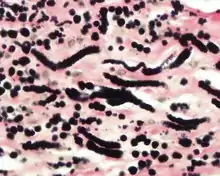

Histochemistry

The elastic fibers will be highlighted by a Weigert or von Gieson elastic stains.[8]